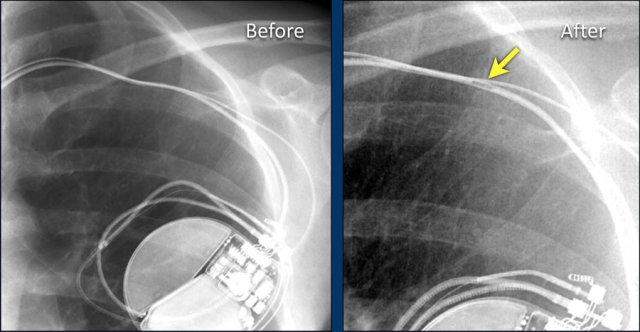

The image is taken immediately after placement of an ICD.

There is a small pneumothorax (arrow).

This is the most common complication.